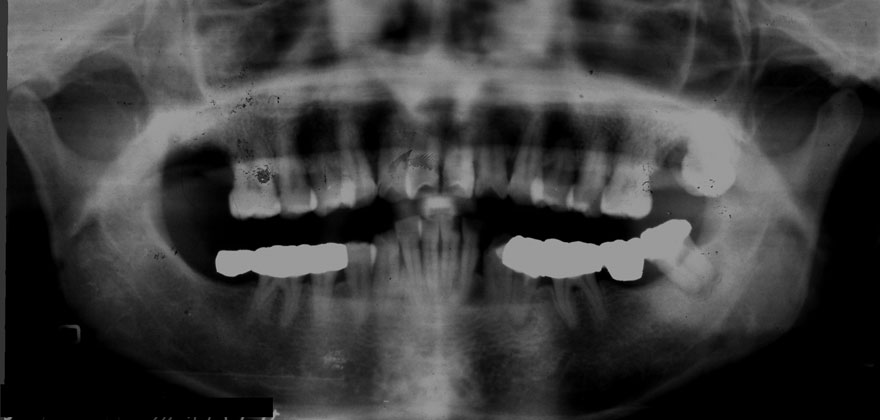

初診時 41歳 男性 平均歯槽骨喪失量:4.11mm

30年後 71歳

平均歯槽骨喪失量:3.70mm

30年間再生量:+0.41mm

年間再生速度:+0.014mm

(ケア頻度:1.27ヵ月ごと)